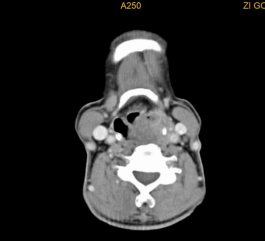

喉癌颈淋巴结转移

声门型喉癌不易发生颈淋巴结转移,声门上型及声门下型则易发生颈淋巴结转移。

常见的还有口咽、口腔、鼻腔鼻窦癌颈淋巴结转移、甲状腺癌颈淋巴结转移等。颈部恶性肿瘤的诊断需要借助详细的病史、全面的体格检查及辅助检查(包括彩超、CT、电子鼻咽喉镜等),最重要的还是要去耳鼻咽喉头颈外科专科就诊。